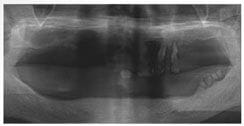

X 光片

術前X光片

術後X光片